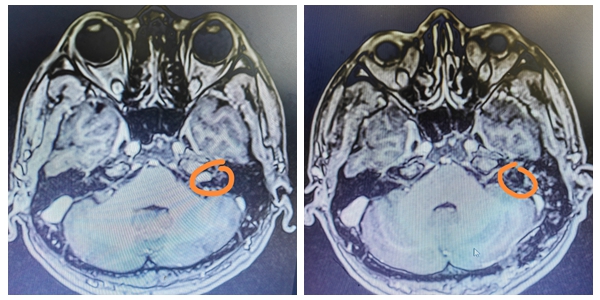

8月29日晚,年仅29岁的董先生突然出现头晕、头痛剧烈、恶心、神志逐渐变差致倒地昏迷不醒,被家属发现后紧急送往湘雅常德医院急诊科。        入院时...